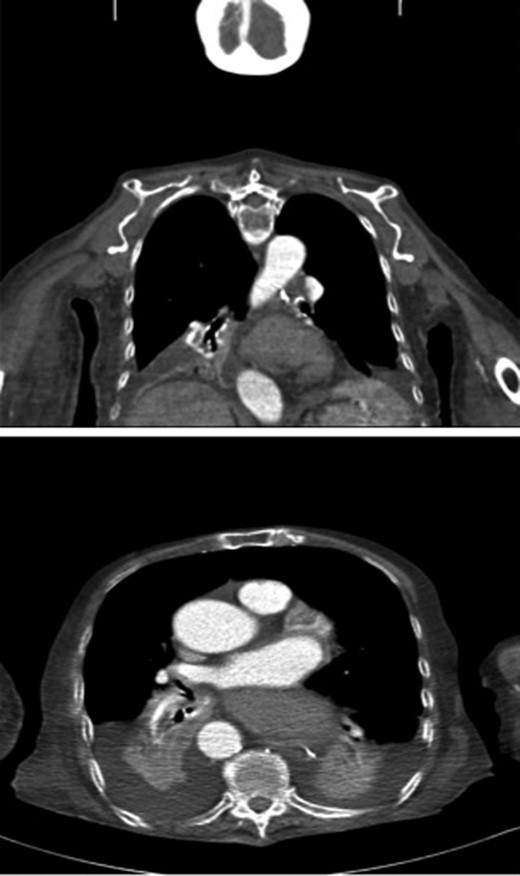

Repeated attempts of NG tube insertion failed due to blockage at the distal oesophagus. A CT scan revealed that an organoaxial volvulus had transmitted through the diaphragmatic hiatus and was occupying the thoracic cavity. No strangulation was noted (Fig. 3). The decision was made to treat the patient conservatively due to the patient's multiple comorbidities and life expectancy.

CT thorax sagittal and coronal views revealed an organoaxial volvulus with the stomach occupying the thoracic cavity. White spot indicating the NG tube tip unable to pass through the volvulus.